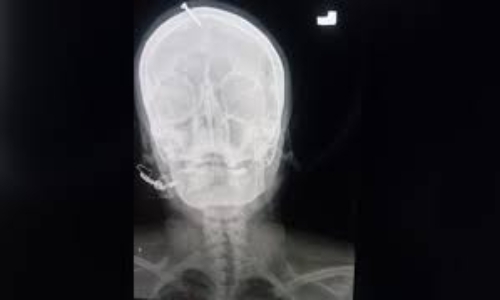

An X-ray showed the five-centimetre (two-inch) nail had pierced the top of the woman's forehead but missed her brain.

Khan said a hammer or other heavy object was used to knock it in.